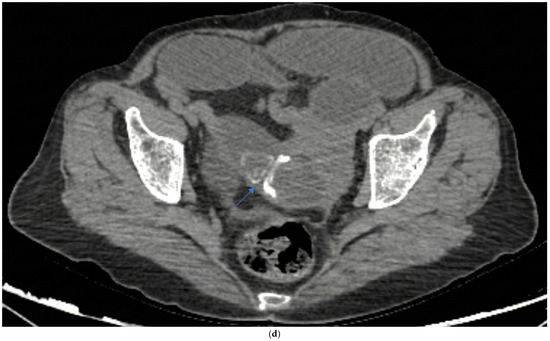

Embryo Sign on Abdominal CT as the Footprint of Cecal Volvulus: Improved Practice Through Lessons Learned from a Case Report

Cecal volvulus is a rare cause of acute abdominal pain, resulting from torsion of the cecum and ascending colon due to abnormal mobility caused by inadequate peritoneal fixation. Clinical presentation is often vague and nonspecific, which can delay diagnosis and treatment. Computed tomography [...] Read more.

Cecal volvulus is a rare cause of acute abdominal pain, resulting from torsion of the cecum and ascending colon due to abnormal mobility caused by inadequate peritoneal fixation. Clinical presentation is often vague and nonspecific, which can delay diagnosis and treatment. Computed tomography (CT) is the imaging modality of choice, as it not only confirms the presence and location of the volvulus but also identifies serious complications such as ischemia or perforation. Abdominal radiographs may be inconclusive, especially when the twisted bowel loop is fluid-filled, aligned antero-posteriorly, or obscured by adjacent gas-filled loops. We present the case of a 65-year-old woman who arrived at the emergency department with sudden-onset abdominal pain. Abdominal CT revealed classic signs of cecal volvulus, including the rarely reported ‘embryo sign,’ which proved crucial for swift diagnosis and intervention. Recognizing both common and less common CT features, such as the embryo sign, is paramount for rapid diagnosis and appropriate management in emergency situations. Familiarity with the full radiologic spectrum of this condition can significantly improve patient outcomes. Full article